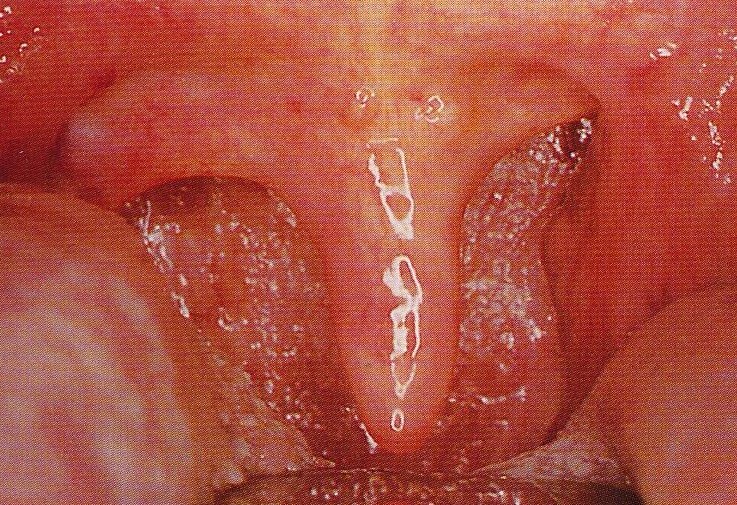

南京耳鼻喉科医院咽喉科医生:根据你描述的情况来看,孩子哼哼的情况说明咽喉有炎症,反复刺激咽喉粘膜,导致咽喉有异物感、有痰的情况,堵塞咽喉,咳不出咽不下,比较难受,所以经常会有清嗓子的情况。从这方面的病情来看是有咽炎的。但是咽炎的性质有很多,如干燥性、肥厚性、萎缩性以及淋巴滤泡增生等,不同性质的咽炎治疗方案都是不一样的。

南京耳鼻喉科医院咽喉科医生:我院专门看耳鼻喉的,所以你的病情情况在我院是很常见的。治疗的方案也是比较多的。针对小孩咽炎建议做咽部内窥镜的检查,明确你咽喉内部具体的炎症程度及具体的病因,结合详细情况制定针对性的治疗方案。